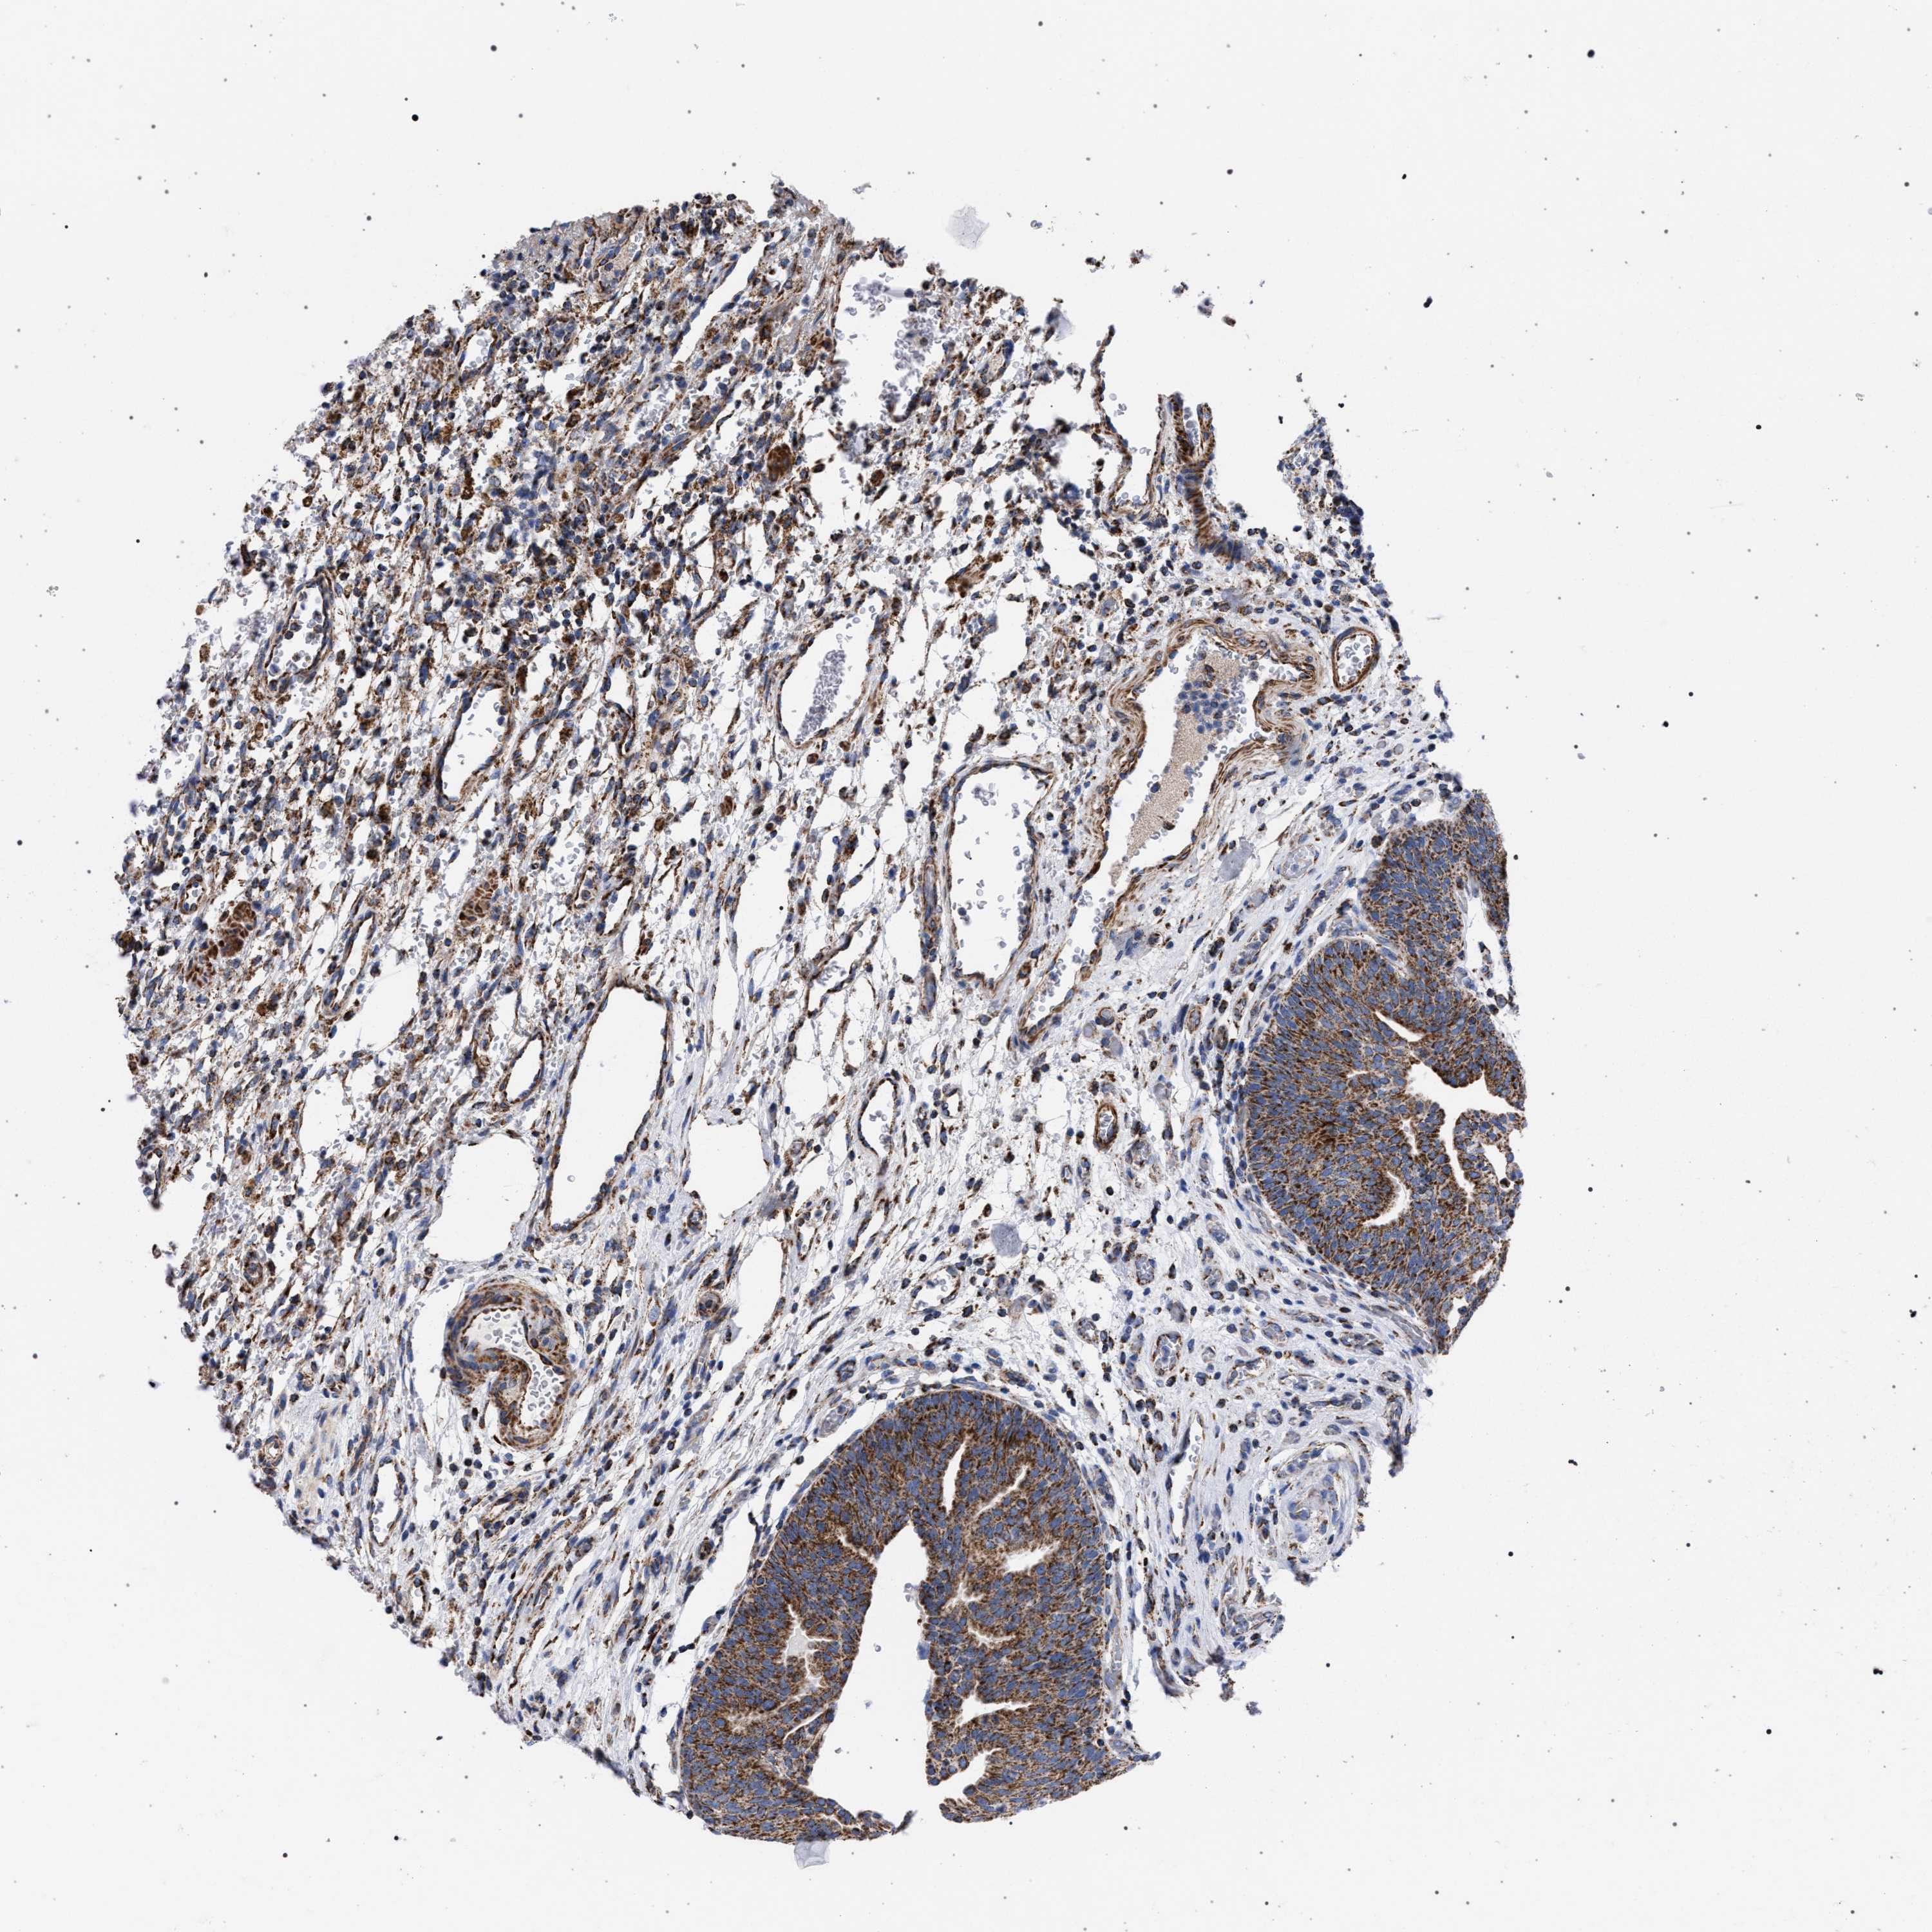

UROTHELIAL CANCER - Protein expressioni

A mouse-over function shows sample information and annotation data. Click on an image to view it in a full screen mode. Samples can be filtered based on level of antibody staining by selecting one or several of the following categories: high, medium, low and not detected. The assay and annotation is described here.

Antibody stainingi

Antibody staining in the annotated cell types in the current human tissue is reported as not detected, low, medium, or high, based on conventional immunohistochemistry profiling in selected tissues. This score is based on the combination of the staining intensity and fraction of stained cells.

Each image is clickable and will lead to virtual microscopy that enables deeper exploration of all samples and also displays staining intensity scores, fraction scores and subcellular localization as well as patient and tissue information for each sample.

Antibody HPA022271

Antibody CAB019284

Staining

High

Medium

Low

Not detected

Intensity

Strong

Moderate

Weak

Negative

Quantity

>75%

75%-25%

<25%

None

Location

Nuclear

Cytoplasmic/membranous

Cytoplasmic/membranous,nuclear

Urothelial carcinoma, Low grade

Urothelial carcinoma, High grade